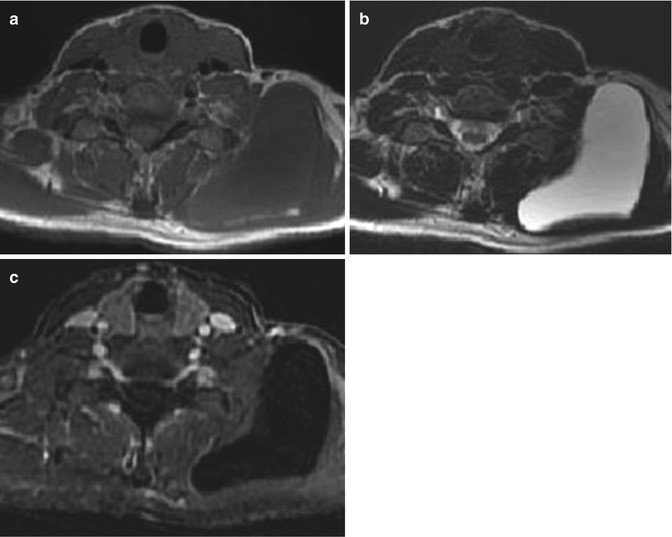

Klippel-Trenaunay syndrome in a 30-year-old boy. (a) Coronal T2-weighted MR image with fat suppression. (b, c) Axial T2-weighted MR images with fat suppression of the pelvis and thigh. (a–c) There is hemihypertrophy of left lower extremity with extensive subcutaneous (star) and intramuscular venous malformations. Note the characteristic abnormal sapheneous vein (arrowhead in c)

Abnormal development of the deep and superficial veins explains persistent embryonic veins including lateral veins with persistent sciatic vein and dilated superficial system. Hypertrophy is variable, affecting the whole leg or only the distal digits [91]. Syndactyly, polydactyly, and congenital hip dislocation can also be observed [92].

On imaging, vascular overgrowth demonstrates slow and late enhancement indicating low-flow malformations. Deep venous malformations of the femoral vein are commonly seen. Because of overgrowth of the soft tissues, the affected limb is usually larger and longer than the unaffected limb [86].